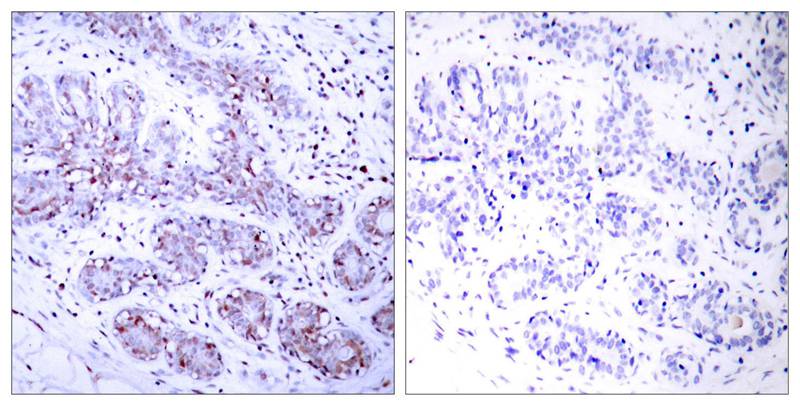

分类: 科研抗体货号: P41251别名: DNA-binding factor KBF2; H2TF1; Lymphocyte translocation chromosome 10; Lyt10; NFKB2应用: WB,IHC,IF反应种属: Human,Mouse,Rat